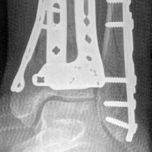

Fig 2.2-5 Intraoperative images.

1. Posterior, anterolateral, and medial plates have been applied. Anatomical reduction and stable fixation of the tibial plafond articular surface has been successfully achieved. At this stage, the fibula had not yet been fixed.

2. Lateral image shows a well-reduced tibial articular surface and a congruent tibiotalar joint.

For definitive fixation, the anterolateral fragment is buttressed with an anterolateral plate and the medial fragment is buttressed with a medial plate. If the plates are longer than the incision, the plates can be slid proximally along the periosteum, and screws inserted using a minimally invasive technique. Large metaphyseal defects should be bone-grafted (Fig 2.2-5).

After pilon fracture fixation is completed, the fibula is fixed. Fibular fixation provides greater stability to the construct. The skin bridge must be considered when placing this third incision, aiming to maximize the distance between it and the vertical limb of the extensile approach and the modified posteromedial approach. The fibula is reduced anatomically and plated (Fig 2.2-6). In situations of tenuous soft tissue, the fibula can be reduced with a mini-open approach and stabilized with an intramedullary rod or screw inserted retrograde from the distal end of the fibula.